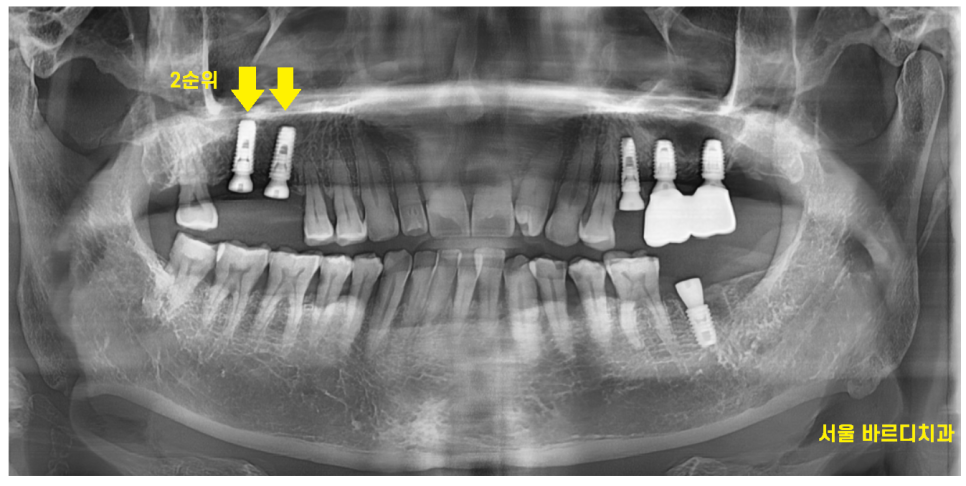

24.03.15

일주일 뒤 수술한 왼쪽 부위 실밥을 뽑는 날

오른쪽 치아가 없던 부위

수술까지 진행하고 가셨는데요.

이왕 서울 올라온김에

방치해둔 왼쪽까지 치료하고 싶다 하셨습니다.

24.07.11

전남 완도에 사시기에

강일동 치과 내원 횟수를 최소한으로

오신 날에 최대한 진료를 많이 진행해드렸는데요.

3월에 수술하고

4개월만에 치료 완료해드렸습니다.